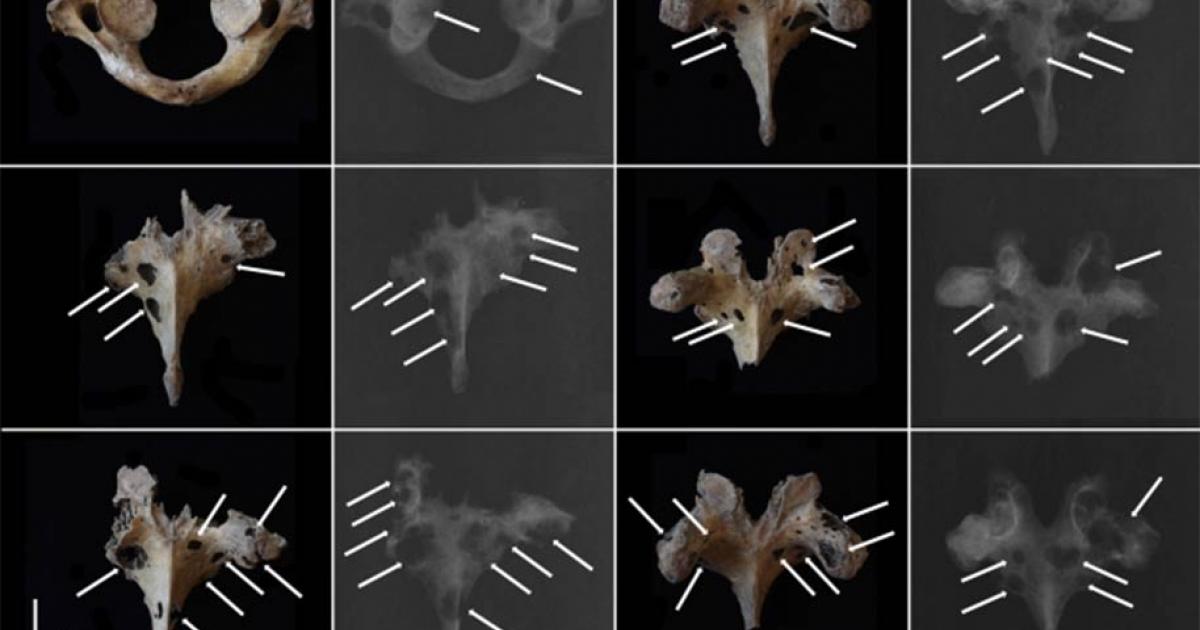

The skeletal remains dating back to Bronze Age China have been analyzed by an international research team. By using a combination of photography and X-rays, they found osteolytic lesions with no sclerosis. They ultimately concluded that these remains are the earliest case of multiple myeloma found to date in East Asia. (Jenna Dittmar / Science Direct)

Photograph (above) and X-ray (below) of the rib shaft of the ancient Bronze Age man showing osteolytic lesions. (Jenna Dittmar / Science Direct)

Top image: Scientists have discovered one of the earliest cases of multiple myeloma, a malignant cancerous tumor, found to date in East Asia within skeletal remains that date back to Bronze Age China. The image shows osteolytic lesions visible on photographs and X-rays of vertebrae. Source: Jenna Dittmar / Science Direct